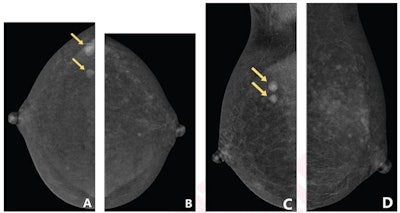

BPE refers to the enhancement of normal fibroglandular tissue on contrast-enhanced imaging. This can make interpreting images more difficult, as well as lead to higher biopsy rates. BPE has been previously reported as impacting CEM interpretation, but the researchers noted that factors influencing the degree of BPE on CEM are not well understood.

For this study, Wang and colleagues explored potential relationships between menstrual cycle and tissue density and the degree of early BPE on CEM. The team included data collected from 207 women between 2020 and 2021. Two radiologists assessed the degree of BPE on CEM as minimal, mild, moderate, or marked. The radiologists also reached consensus for breast density on CEM, and their overall agreement was measured by kappa coefficients.

Wang et al found that interreader agreement for degree of BPE was 0.80, and they noted positive associations between dense breasts and premenopausal status with irregular menstrual cycles. For premenopausal women with regular cycles, the degree of BPE was lowest for women in menstrual cycle days eight to 14.